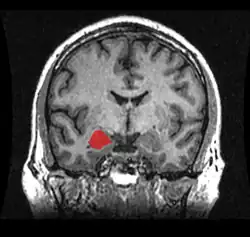

Amygdala

Die Amygdala oder der Mandelkern ist ein paariges Kerngebiet des Gehirns im zur Mitte gelegenen Teil des jeweiligen Temporallappens. Sie ist Teil des limbischen Systems. Der Name der Amygdala (fachsprachlicher Plural: Amygdalae) ist nach ihrem Aussehen aus lateinisch amygdala, dies aus altgriechisch ἀμυγδάλη ‚Mandel(kern)‘, geschöpft. Sie wird auch als Corpus amygdaloideum bezeichnet.